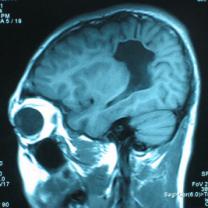

结果及随访:术后一周复查头颅CT显示脑室穿通畸形明显缩小(图6)。随访3年,未出现癫痫发作。得到很好的治疗,回归社会,正常生活学习工作。

图6:术后一周复查头颅CT显示脑室穿通畸形明显缩小